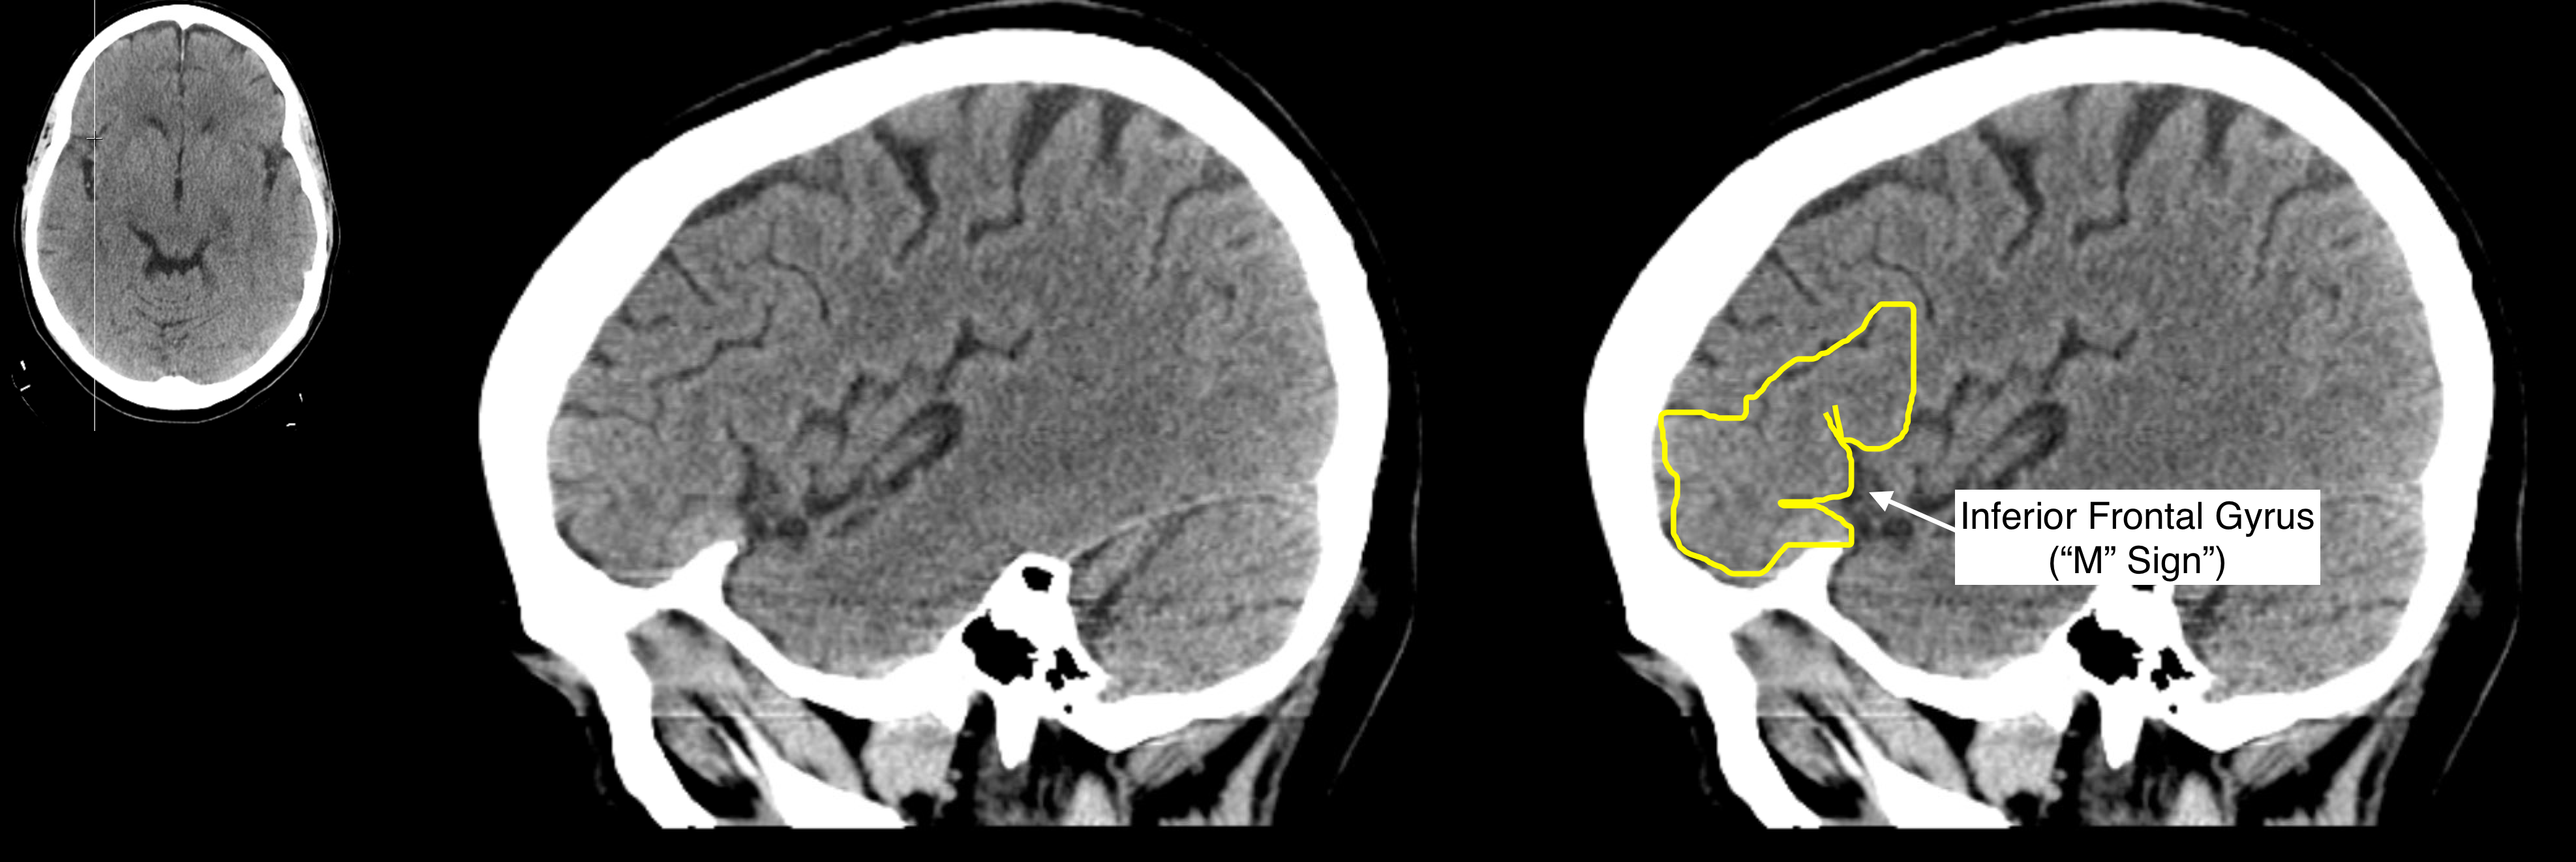

Radiological Anatomy Inferior Frontal Gyrus Stepwards Brain Gyrus Labeled Mri A review of brain magnetic resonance imaging (mri) is used as support. Brain mri with annotations of major structures. The anatomy of the brain is studied by means of axial, coronal and sagittal views. We shall also explore the anatomy of the 12 pairs of cranial nerves and anatomic variants without pathologic significance, relying mainly on. The main indications for. Brain Gyrus Labeled Mri.

Radiological Anatomy Inferior Frontal Gyrus Stepwards Brain Gyrus Labeled Mri Brain mri with annotations of major structures. The main indications for tailored. Specifically on the frontal cortex, we can. The anatomy of the brain is studied by means of axial, coronal and sagittal views. We shall also explore the anatomy of the 12 pairs of cranial nerves and anatomic variants without pathologic significance, relying mainly on. A review of brain. Brain Gyrus Labeled Mri.

Radiological Anatomy Inferior Frontal Gyrus Stepwards Brain Gyrus Labeled Mri The superior frontal gyrus is the medial most gyrus of the frontal lobe's superolateral surface, running from the frontal pole anteriorly,. Explore our video tutorial, quizzes, articles and labeled diagrams on this topic. Specifically on the frontal cortex, we can. Mri is the preferred imaging technique to assess hippocampal anatomy and pathology. The anatomy of the brain is studied by. Brain Gyrus Labeled Mri.